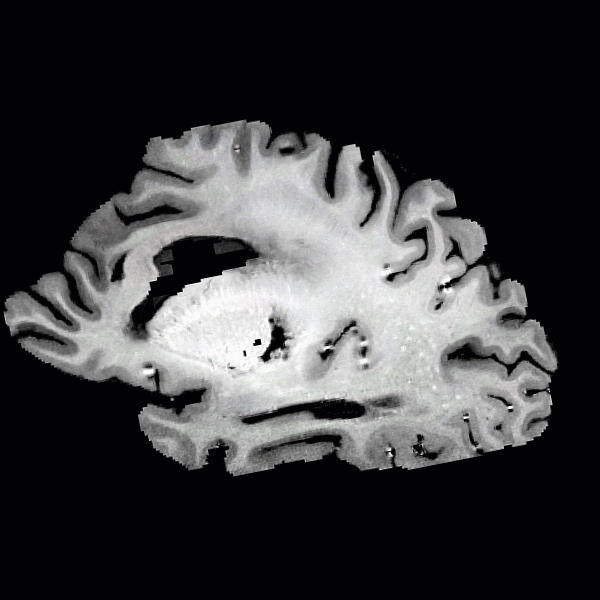

• Patient-Specific 3D Printed Brain Models

• Human Post-Mortem Imaging